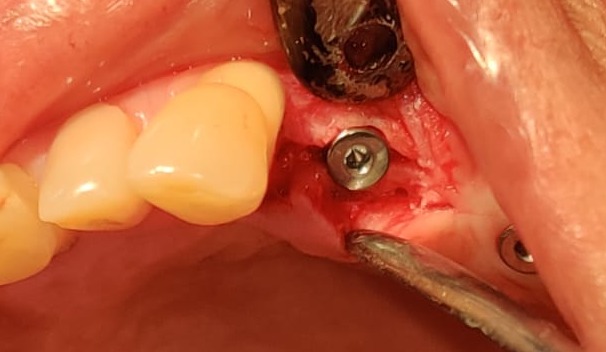

It was really challenging case. Delayed implantation with highly resorbed bone.

It was acid test for osseosure to create osteotomy without fracturing bone. and osseosure did it .

implant went with 40 NCm torque.